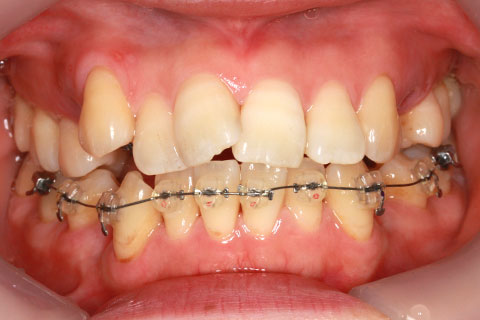

治療中(開始直後)

- 年齢・性別

- 25歳女性

- 治療期間

- 2年0ヶ月

- 抜歯

- 上下4番抜歯

- 治療費

- 110万円

- 治療内容

- 施術の副作用(リスク)

- 表側矯正と比較して、力学的な操作性が複雑なため、ボーイングエフェクトを起こしやすい。